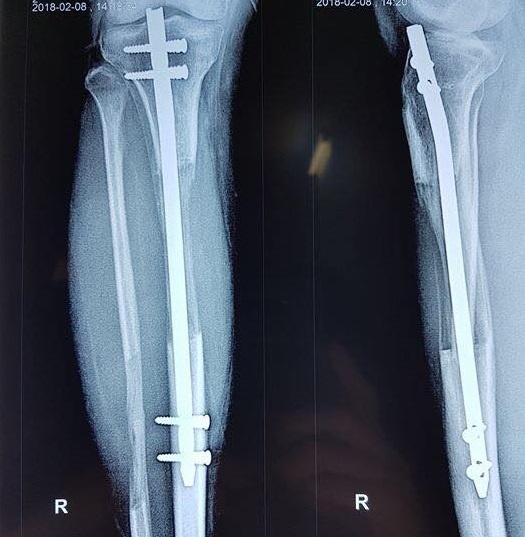

| Hình ảnh chụp phim kiểm tra sau ngừng kéo, bắt chốt 3 tháng của bệnh nhân Nam. Chiều cao tăng lên 10 cm. Ảnh: Bác sĩ cung cấp. |

“Sau 70 ngày, Nam đã tăng thêm 7 cm. Chúng tôi vẫn khuyên các bệnh nhân chỉ nên dừng lại ở con số này để hạn chế thấp nhất các biến chứng. Tuy nhiên, khi đạt chiều cao này, bệnh nhân vẫn quyết tâm xin được tiếp tục kéo dài. Khi kiểm tra đủ điều kiện, Nam đã tiếp tục tới 100 ngày mới dừng với chiều cao tăng thêm 10 cm”, PGS Đoàn chia sẻ.

Tháng 2, Nam đã được tháo khung và đinh, có thể đi lại bình thường với sự trợ giúp của nạng. Nam sinh đã quay lại Nhật để tiếp tục việc học chỉ sau 7 tháng.